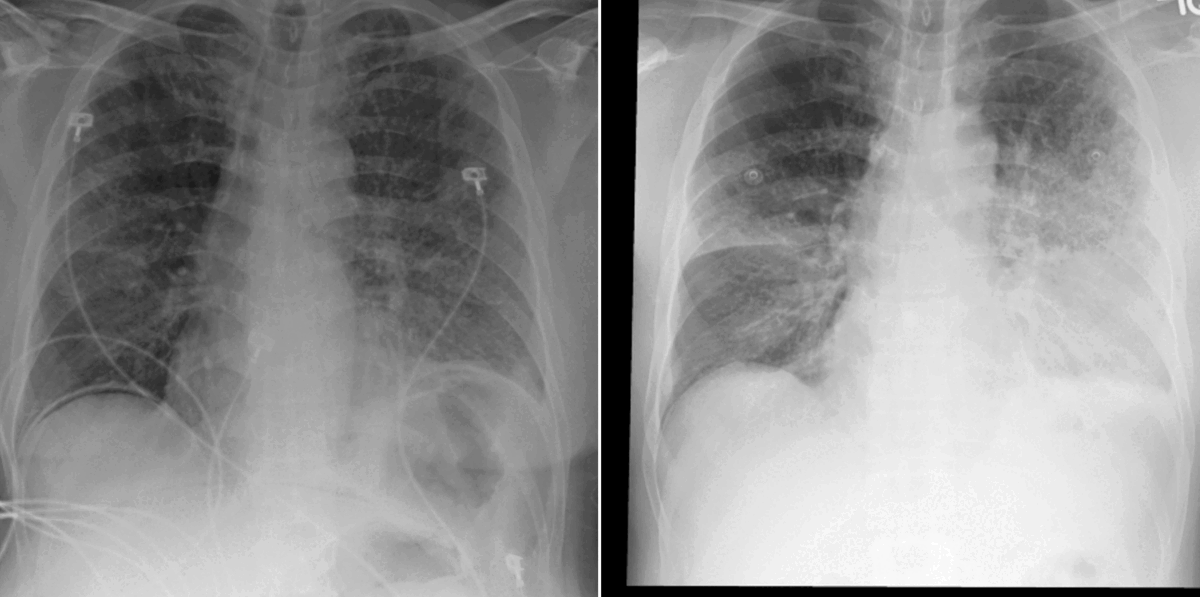

Figure 2: Example of current (left) and prior (right) chest X-ray scans. The attention maps computed within the vision transformer show (in purple) how the model interprets disease progression by focusing on these image regions. In this particular example, the airspace disease seen in the left lung lobe has improved since the prior acquisition.